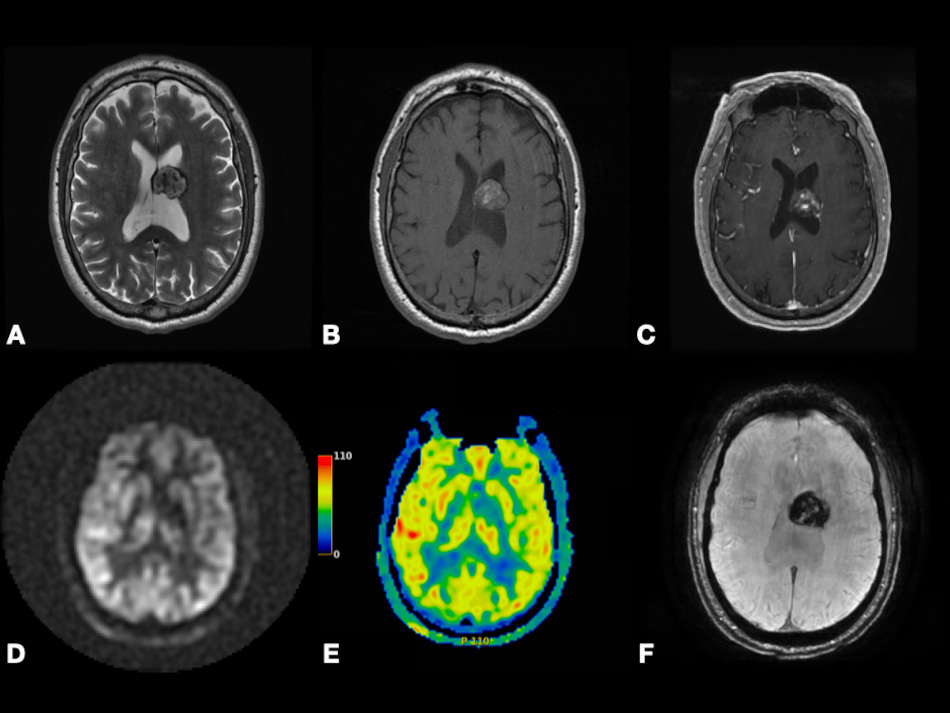

In Fig. 8, we present a case of right frontal lobe non-small cell lung cancer MT. Color-coded CBF map from pcASL data and color-coded rCBV map from DSC data show heterogenous hyperperfusion amongst nodules at super lesion margin and enhancing margins elsewhere. This demonstrates that MTs may show hyperperfusion using ASL or DSC. This highlights the importance of using quantitative parameters, such as tumoral and peritumoral CBV and CBF to compare between GBM and MTs as depending on observing hyperperfusion signals on the color-coded maps is subjective and can be misleading.

Fig. 8.Right frontal lobe non-small cell lung cancer metastasis. Axial SWI (A), FLAIR (B), and post-contrast T1-weighted (C) images depicting lesion with heterogenous enhancement, perilesional vasogenic edema, central necrosis, and intralesional hemorrhage. Axial pcASL source data (D), color-coded CBF map (E) from pcASL data, and color-coded rCBV map (F) from DSC data depicting heterogenous hyperperfusion amongst nodules at super lesion margin (red arrowheads) and enhancing margins elsewhere (yellow arrowheads). Abbreviations: SWI, Susceptibility weighted imaging; FLAIR, Fluid attenuated inversion recovery; pcASL, Pseudo-Continuous Arterial Spin Labeling; CBF, cerebral blood flow; rCBV, relative cerebral blood volume; DSC, Dynamic susceptibility contrast MR imaging.